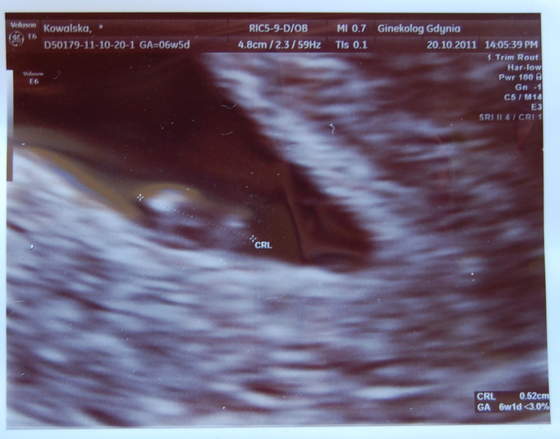

śliczne malenstwo ahh :*